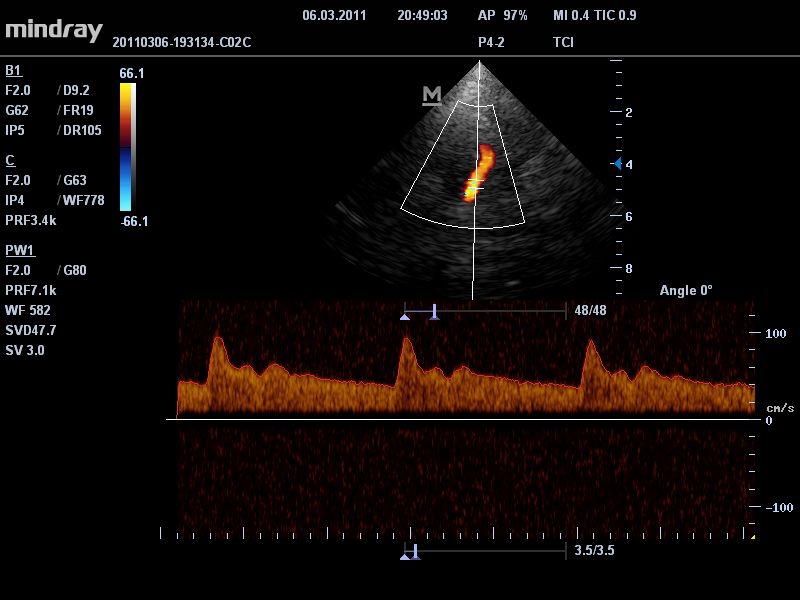

• Режимы сканирования: B/M/CFM/PDI/Направленный PDI/PW, HPRF, Тканевая гармоника, М- и цветной М-режим.

• TDI: тканевый допплер с количественным анализом.

• Секторный фазированный датчик Mindray P7-3